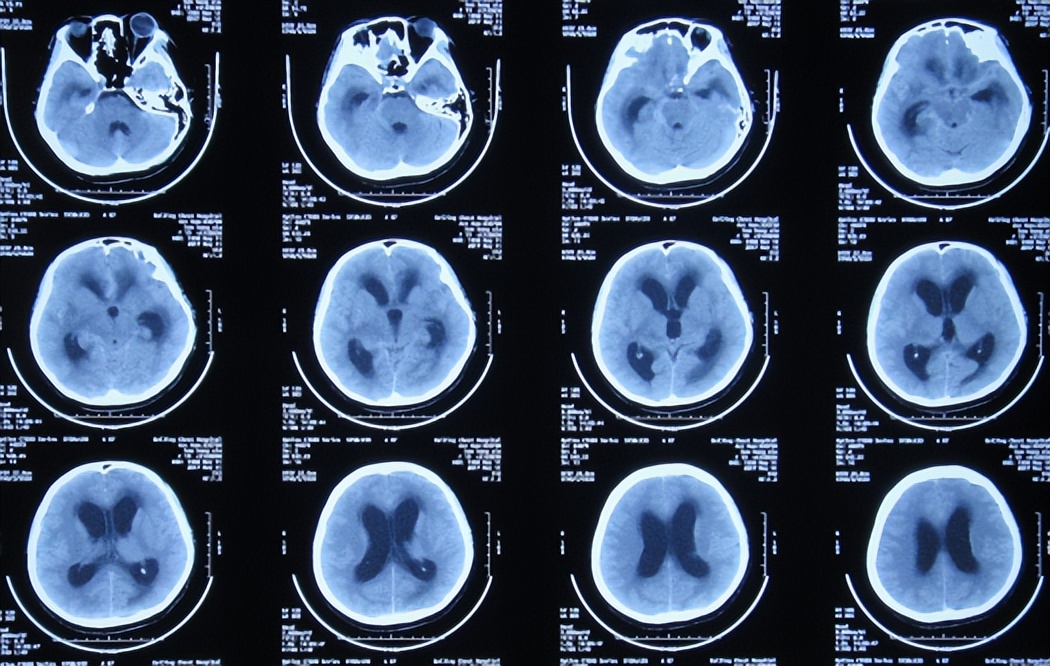

2017年5月11日(第4家医院入院治疗6天),颅压降至185mmH2O,体温变正常,但左眼睑下垂无改善,出现头痛,查头颅CT示脑室扩张( 图-7 );考虑结核脑膜炎性脑积水。

图-7: 2017年5月11日脑CT